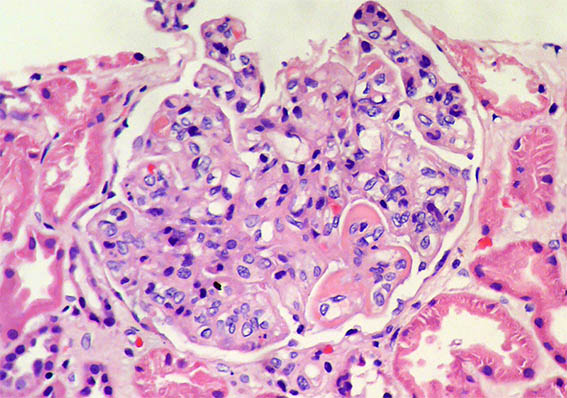

Figure 2. H&E, X400. In this glomerulus there is endocapillary hypercellularity, in addition, subendothelial deposits in the lower right corner.